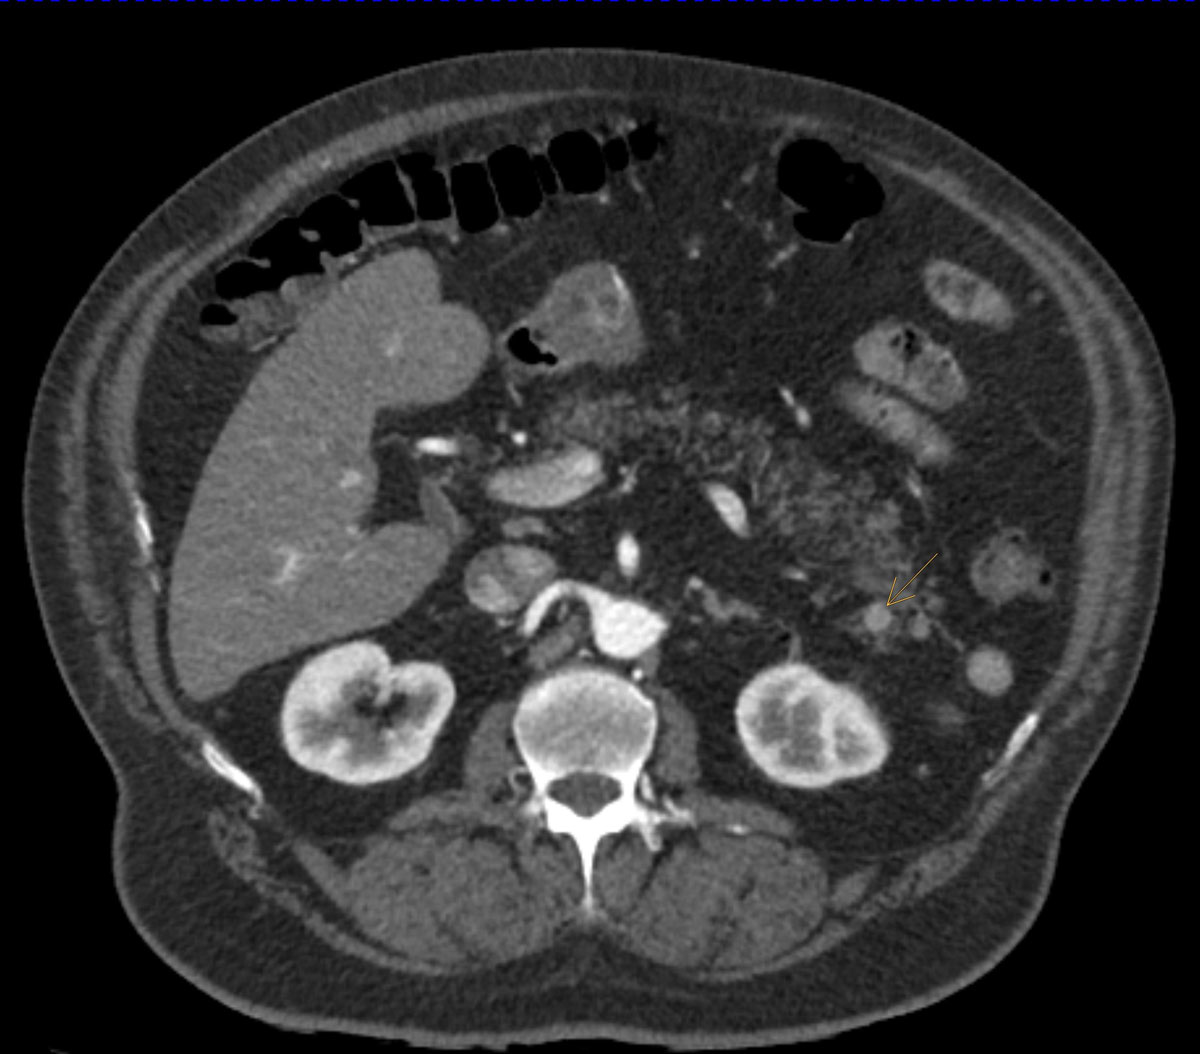

A total of 85/200 patients (42.5%) exhibited incidental findings requiring immediate further medical workup and/or treatment. Of note, most incidental findings here were newly diagnosed cardiovascular conditions, with coronary artery calcification being the most prevalent finding followed by arterial aneurysms and incidentally detected embolism (table 2, figs 1, 2a and 2b ). Pancreatic and liver tumours were less frequent, but significant. Examples of incidentally diagnosed tumours are shown in figures 3 and 4 .

Figure 3 Axial CT scan of a neuroendocrine pancreatic tumour incidentally diagnosed in a 67-year old ED patient.

Figure 4 Axial CT scan of a bladder tumour incidentally diagnosed in a 62-year old ED patient with a history of cigarette smoking and cerebrovascular disease.

Tumour findings deemed to require immediate attention were observed in 3% in our sample population. Thus, the CT scan changed treatment pathways in a considerable number of patients in the present series, based on suspicion of neoplasm [28]. This finding is not entirely new since it was previously shown that the incidence of cancer 5 years after an ED diagnosis is significantly higher when compared with that of the general population [29]. This finding further supports the medical burden associated with ED.